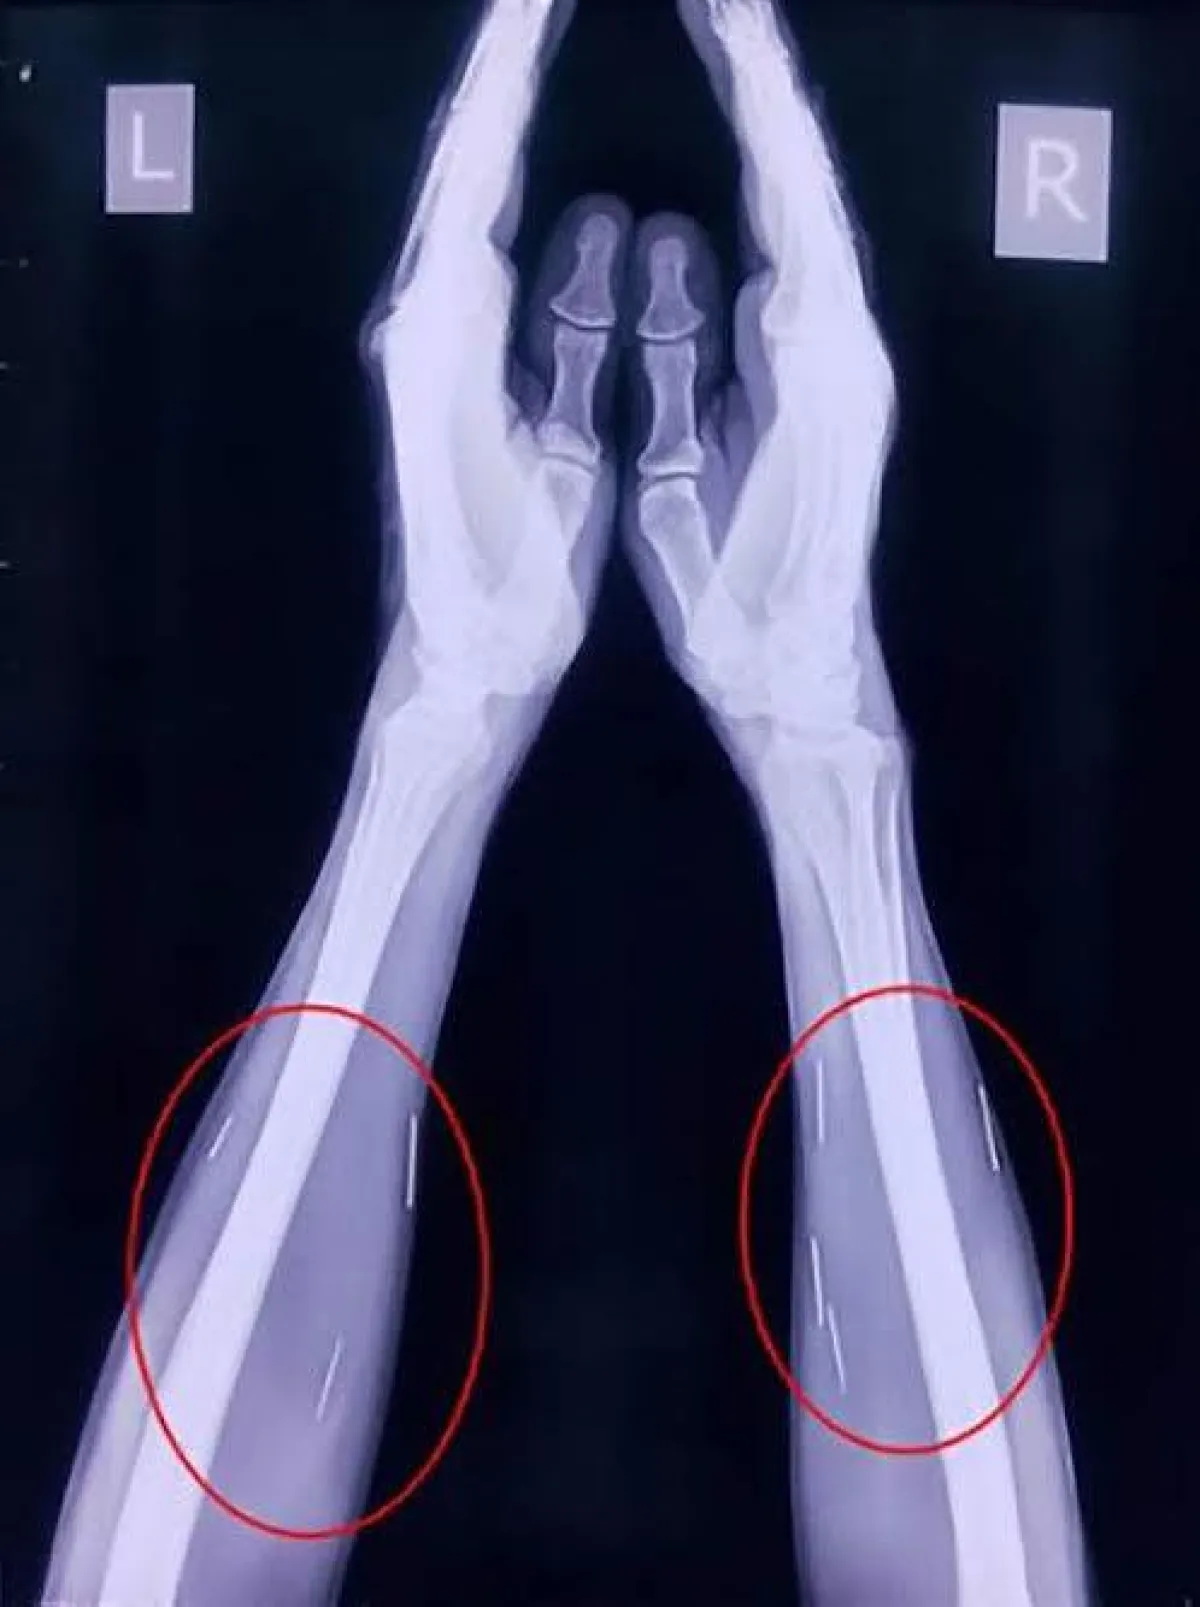

ويرقد الرجل حالياً في مستشفى "مومباي" استعداداً لإجراء الجراحة، التي سيتم خلالها ازالة 40 مسمار من الحلق و 25 من ساقه اليمنى و10 من أماكن متفرقة باليدين وباقي الجسد .

وقال إبنه "راجندرا": "اعتقدنا أن الأمر بسيط، ولكن شعرنا بالخوف بعد رؤية صور الاشعة ونحن لا نعرف كيف دخلت تلك المسامير، ووالدي نفسه لا يتذكر كيف حصل ذلك، وأكد الأطباء أن تلك المسامير لم تؤثر على وظائف حيوية في جسده".